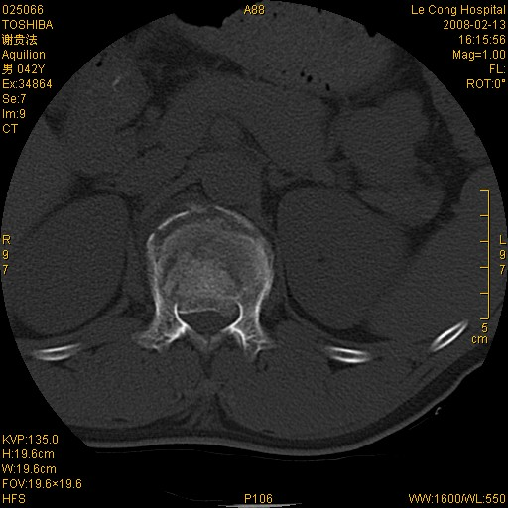

爆裂型骨折CT表现

·能清楚看到椎体骨折线部位、走行、粉碎性骨折片分布,呈波浪状、放射状、线状、不规则。

·椎板骨折

·骨性椎管变形狭窄,断端累及三柱或其中二柱,累及椎体后壁及椎板,骨块可突出椎管,导致椎管狭窄 。椎管狭窄分度(0,I, II, III)

·脊柱爆裂性骨折其椎体前后均有不同程度压缩,楔形

·CT诊断时爆裂性骨折,注意椎管分度